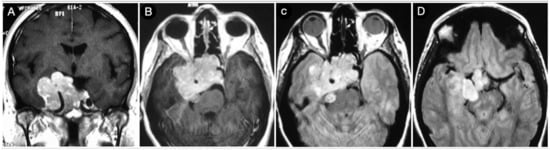

Case #1: Infradiaphragmantic Tumor with Middle Fossa Involvement through the Cavernous Sinus